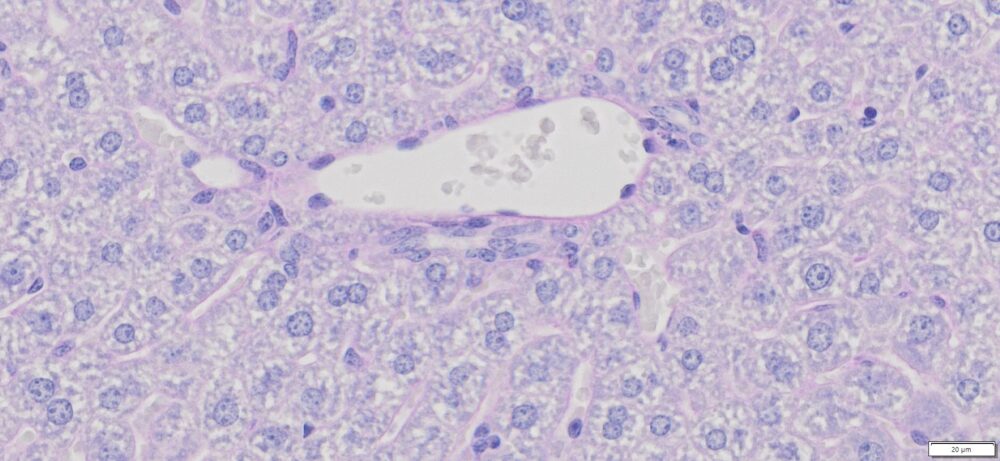

Expected Results

- Mucins—————————–Magenta

- Nuclei——————————Dark Blue

- Glycogen————————–Not stained (glycogen is removed by diastase digestion)

More PAS-Diastase (PAS-D) Staining Images